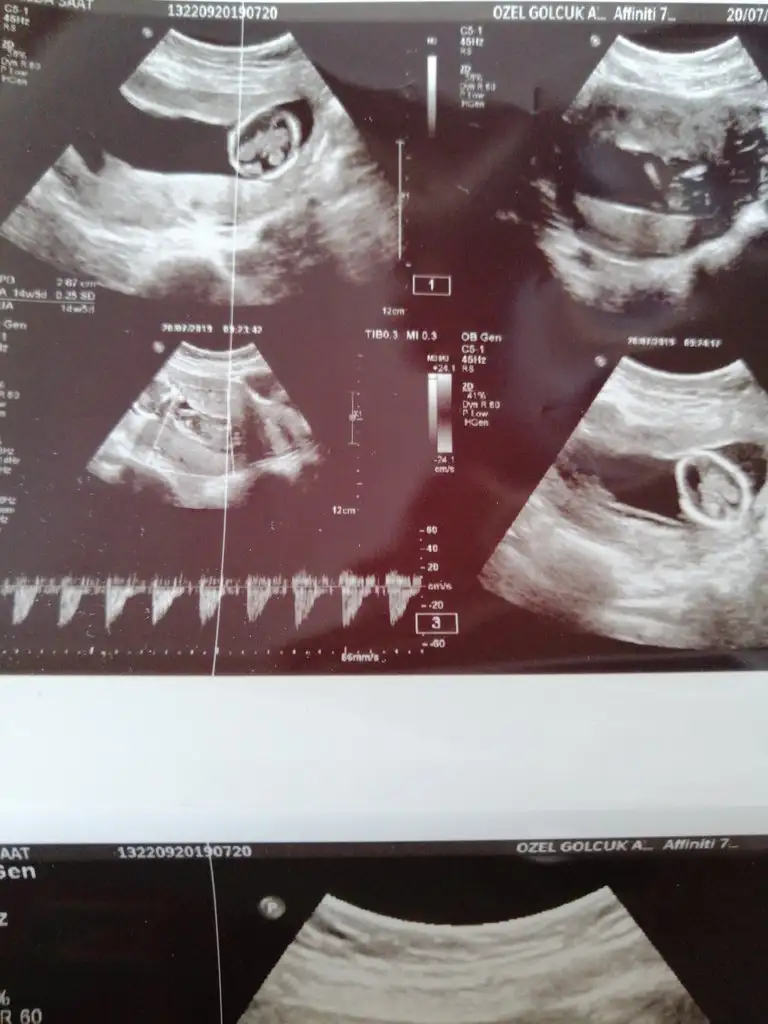

rica etsem Bakabilir msiniz nuba göre :))Eki Görüntüle 2290731 Eki Görüntüle 2290732